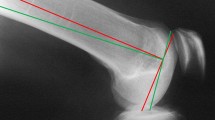

a CAS extension gap balancing. A computer screen image shows virtual extension gap balancing to obtain a rectangular extension gap and a knee mechanical axis with 0° of varus or valgus. b CAS flexion gap balancing. A computer screen image shows virtual flexion gap balancing to obtain a rectangular flexion gap equal to the extension gap; a 1° of internal TEFR was needed in this case. c Posterior referencing cutting guide and the CAS tracker. The free active wireless tracker was inserted into a posterior referencing cutting guide to determine the PRFR value in this device that was equivalent to the previous TEFR value in the same knee during the same surgical procedure. We subtracted 3° of external rotation from the posterior referencing cutting guide femoral rotation to obtain the rotation of this device (in degrees) that balances the flexion gap in relation to the optimal value of 0° of the established CAS transepicondylar axis. This rotation was called the posterior reference femoral rotation (PRFR)

Among the 36 patients in the FB-CAS group, the TEFR was obtained as the rotation in degrees that balanced the flexion gap in relation to the optimal value of 0° of the established CAS transepicondylar axis (Fig. 1b). Once the TEFR was determined, the free active wireless tracker was inserted in a posterior referencing cutting guide to determine the rotation value of the cutting guide that was equivalent to the previous TEFR value in the same knee during the same surgical procedure (Fig. 1c). Assuming that there was a consistent relationship of 3° of ER between the transepicondylar axis and the posterior condylar axis, in an ideal situation 3° of ER of the posterior referencing cutting guide corresponds with 0º of rotation about the transepicondylar axis. We subtracted 3° of ER from the posterior referencing cutting guide rotation to obtain the rotation in degrees that balanced the flexion gap in relation to the optimal value of 0° of the established CAS transepicondylar axis. This rotation was called the posterior reference femoral rotation (PRFR).